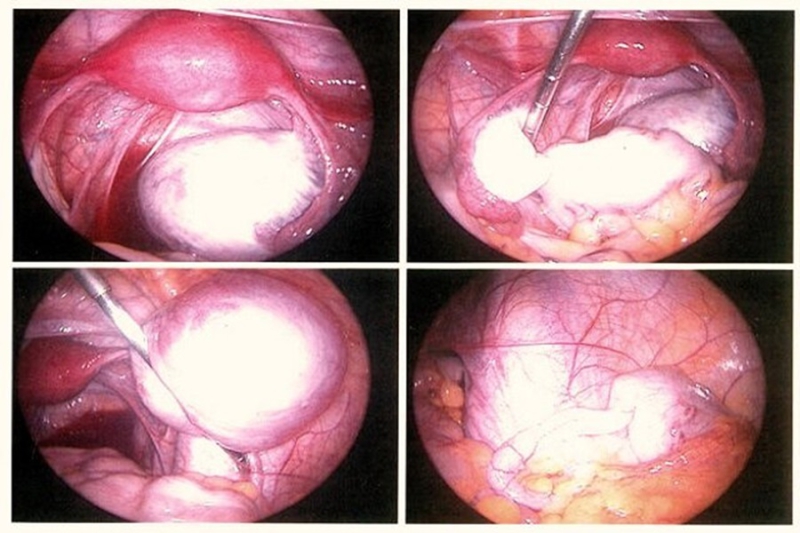

پادمهر افزود: یکی از ویژگیهای خاص این کنگره، برگزاری جراحی زنده است که برای جراحان در سراسر دنیا یک چالش محسوب میشود. ما با همکاری مرکز ناباروری ابن سینا و پژوهشگاه سینا، توانستهایم از جدیدترین تجهیزات لاپاراسکوپی و جراحی مینیمالی اینویزیو برای درمان بیماران آندومتریوز استفاده کنیم. در این کنگره، جراحی زندهای با حضور دکتر ربیعی، جراح مینیمالی اینویزیو از کشور عراق، برگزار خواهد شد. این جراحی به روش لاپاراسکوپی انجام میشود، چرا که متأسفانه به دلیل تحریمها، هنوز امکان استفاده از سیستمهای رباتیک در ایران وجود ندارد. امیدواریم که بهزودی با کمک شرکتهای دانشبنیان داخلی، این فناوریها در کشور تولید و در درمان آندومتریوز مورد استفاده قرار گیرند.